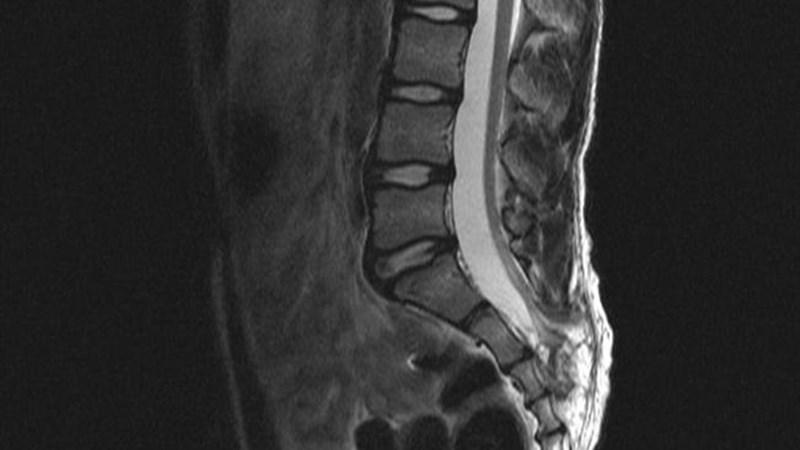

С помощью МРТ можно определить наличие синусопатии, основываясь на изменениях слизистой оболочки. Кроме того, магнитно-резонансная томография поможет выявить наличие опухолей.